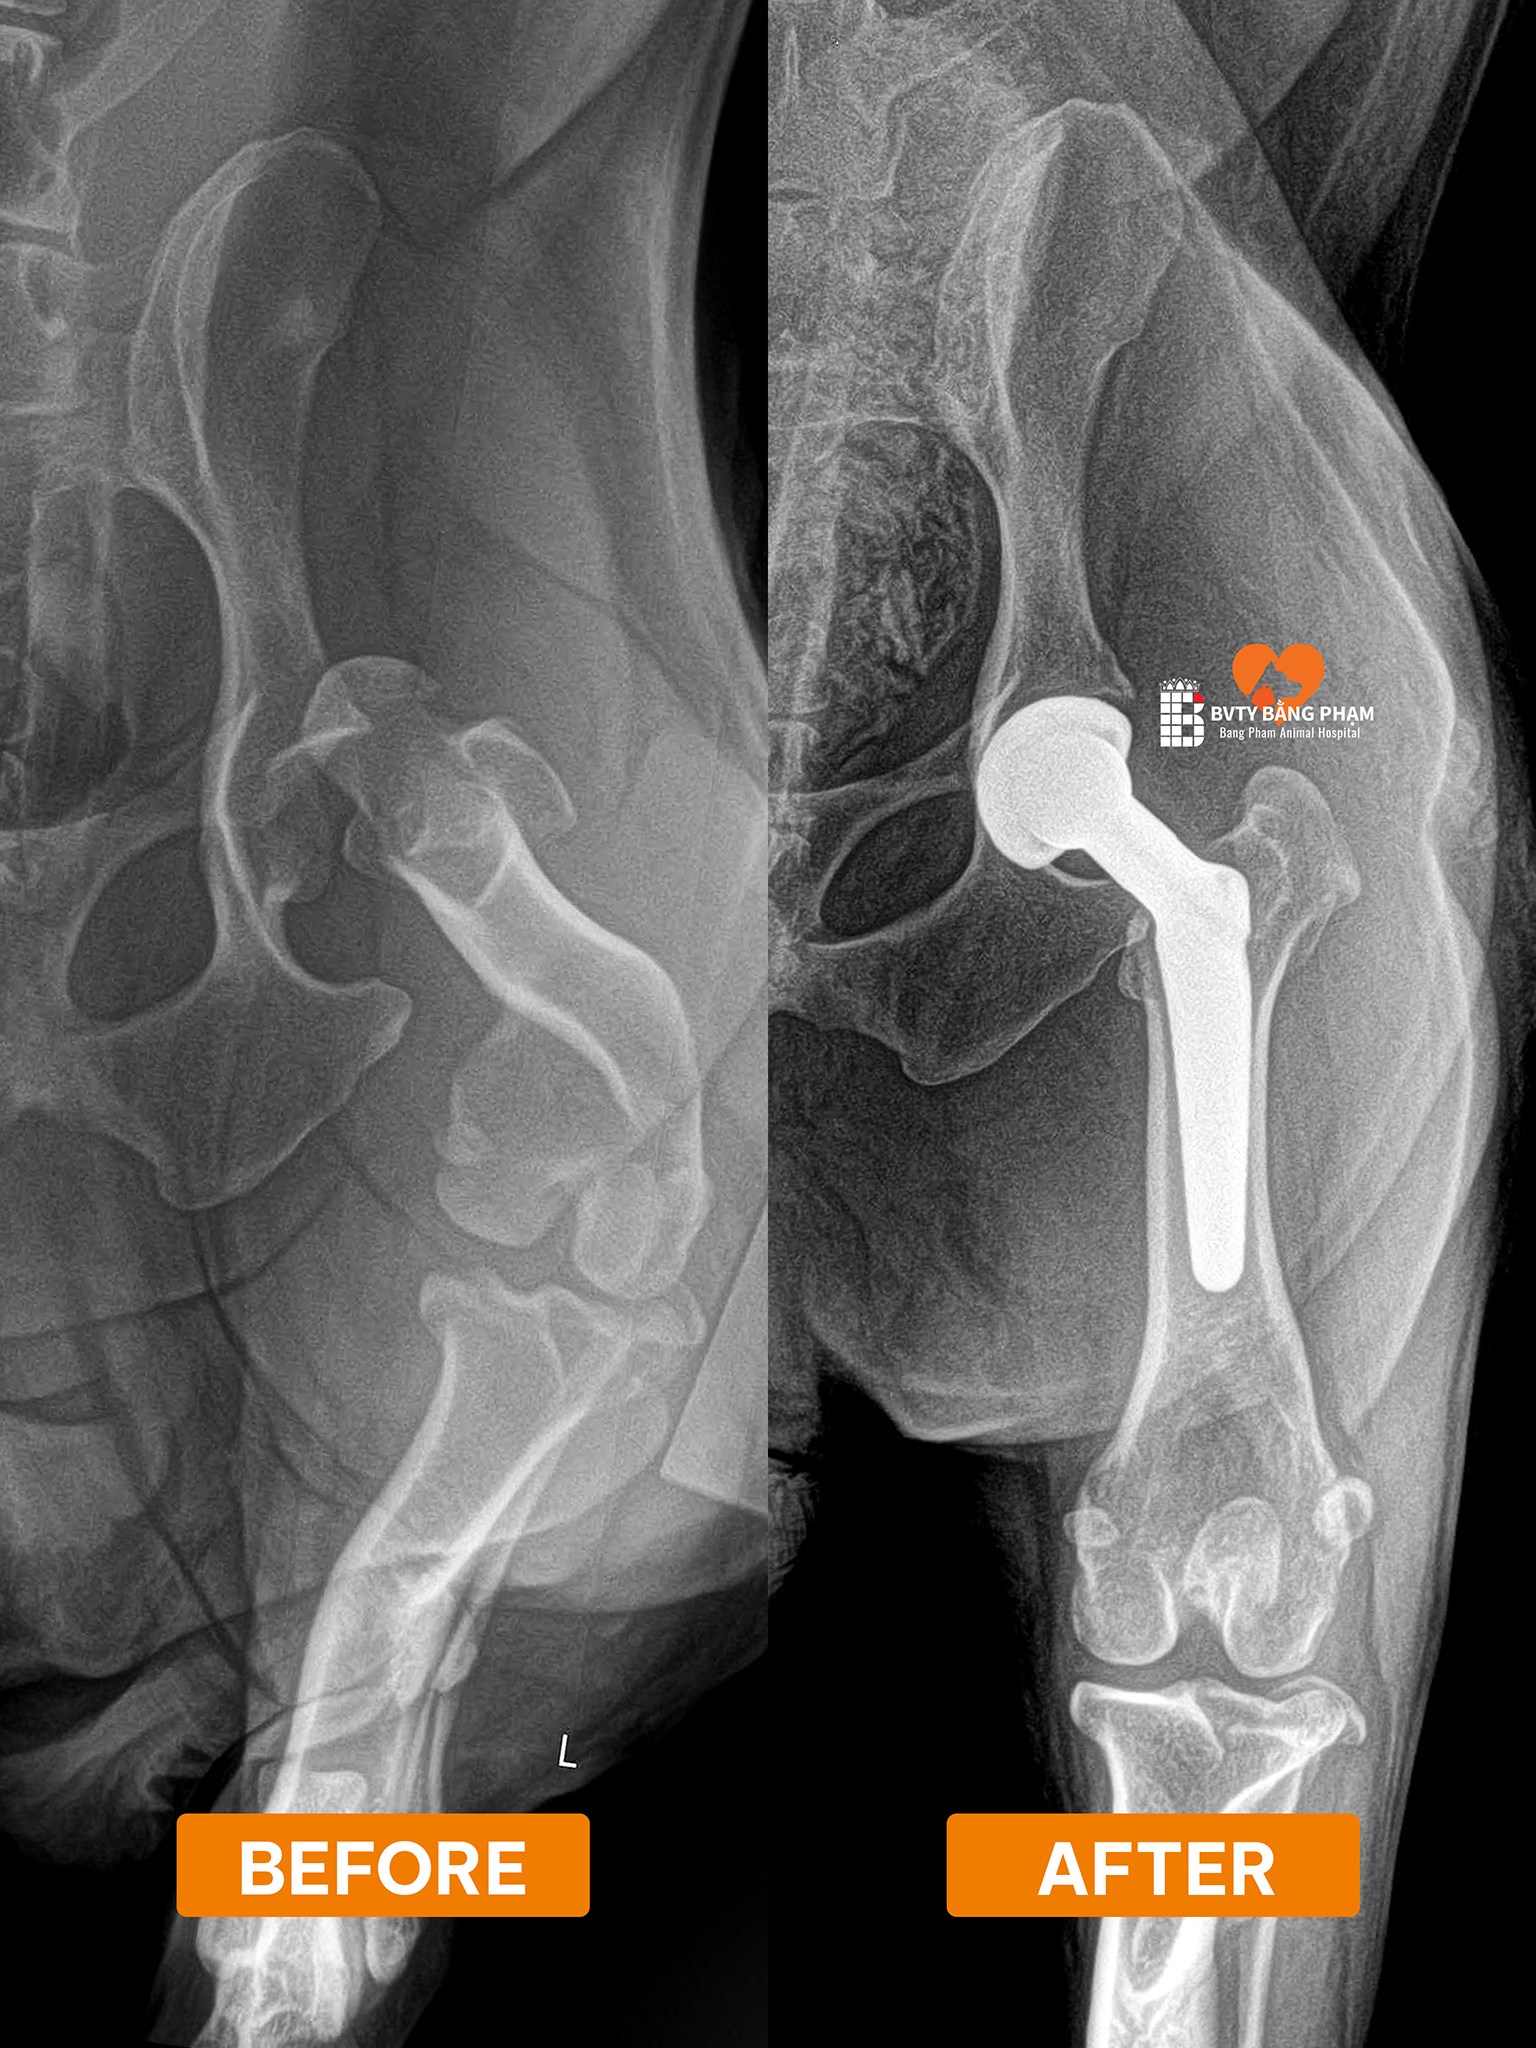

Qua quá trình thăm khám lâm sàng và chụp X-quang, các bác sĩ tại Bằng Phạm đã chẩn đoán chính xác: Bum bị đứt dây chằng khớp háng hoàn toàn.

Về mặt giải phẫu, dây chằng khớp háng đóng vai trò như một “dây neo” vô cùng quan trọng, giúp giữ chặt chỏm xương đùi nằm yên vị trong ổ cối xương chậu. khi chó bị đứt dây chằng khớp háng, toàn bộ cấu trúc khớp háng sẽ trở nên lỏng lẻo, dẫn đến tình trạng trật khớp, tê liệt vận động và gây ra những cơn đau dữ dội. Đứng trước chấn thương nghiêm trọng này, việc can thiệp ngoại khoa là con đường duy nhất để giải cứu Bum.

Sau khi hội chẩn, các bác sĩ chỉ định thực hiện Phẫu thuật Thay khớp háng toàn phần (Total Hip Replacement – THR). Đây được xem là “tiêu chuẩn vàng” trong việc điều trị các chấn thương khớp háng nặng nề với 3 mục tiêu cốt lõi: loại bỏ hoàn toàn cơn đau, tái tạo cấu trúc giải phẫu ổn định và phục hồi chức năng vận động tối đa.

Ca đại phẫu được thực hiện với sự hỗ trợ của bộ dụng cụ chuyên dụng BlueSAO. Quy trình đòi hỏi sự chính xác tuyệt đối, bao gồm các bước:

• Tiếp cận vùng khớp háng, tiến hành cắt bỏ toàn bộ các phần xương và sụn đã bị tổn thương.

• Lắp đặt một ổ cối nhân tạo để thay thế cho phần ổ cối tự nhiên.

• Thay thế chỏm xương đùi cũ bằng một chỏm kim loại cao cấp, có chân cắm vững chắc vào trong lòng xương đùi.

• Cuối cùng, lắp ghép hai bộ phận nhân tạo này lại với nhau để tạo thành một khớp háng mới, đảm bảo độ vững chãi và biên độ vận động linh hoạt.